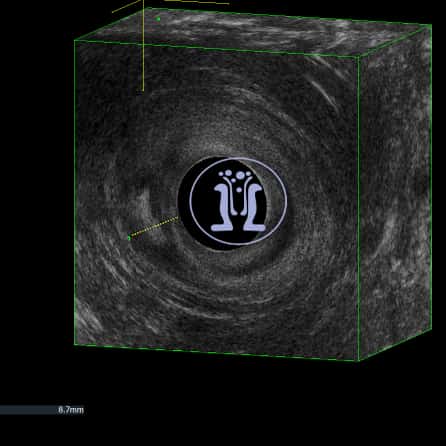

Ενας χειρουργός, μας ζητησε την βοήθεια του για την θεραπεία ενός εμφανούς και απλού συριγγίου σε εύσωμο άνδρα ασθενής 42 ετών. Κάναμε την χαρτογραφηση των σφιγκτήρων και του συριγγίου και καθοδηγήσαμε τον συνάδελφο για την σωστή θεραπεία της περίπτωσης.